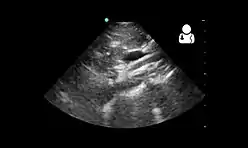

Upper gastrointestinal series showing extreme duodenal dilation (white arrow) abruptly preceding constriction by the SMA.- Ultrasound showing SMA syndrome[19]

Ultrasound showing SMA syndrome[19]